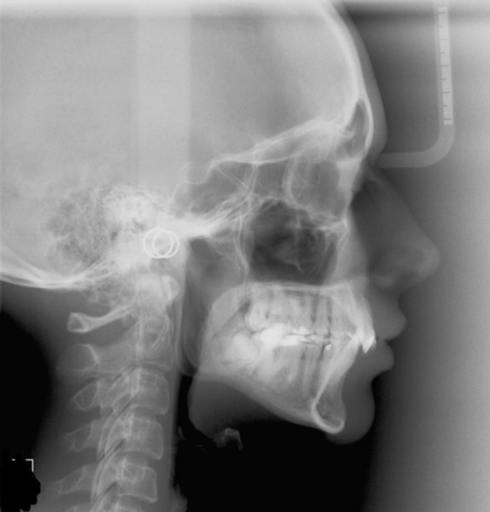

A friend was just diagnosed with ossifying fibroma of the mandible. She woke up one morning with an obvious swelling around the area of the lower left row of teeth. Very hard, but painless and also presenting under the tongue and starting to shift teeth. The first oral surgeon recommended removal, soon. The ENT doctor recommends a second biopsy to detect estrogen content. If estrogen is found, he wants to put her on estrogen suppressant drugs (she is 50 yrs old). She is at a world class teaching institution, with supposedly the best of the best, yet this is not a common diagnosis and we are not sure what to do. Your opinion would be greatly appreciated.